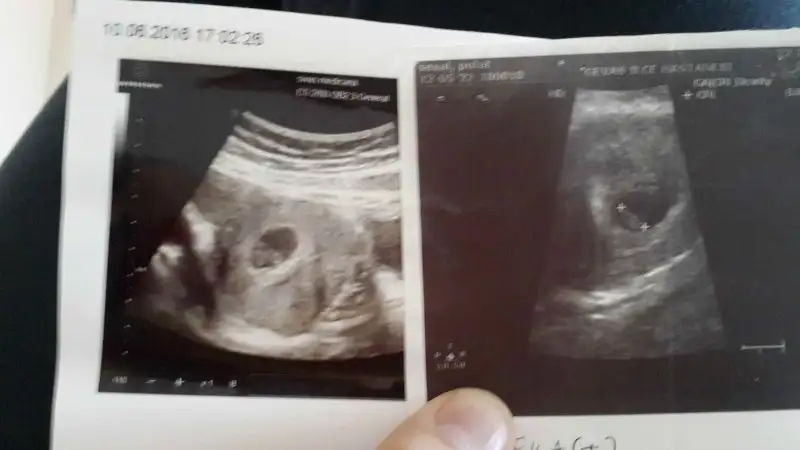

Canım sana zahmet olmazsa bize de bakabilir misin? Soldaki yeni bebeğim sağdaki oğlumun ultrason görüntüsüydüHavalianne__

Eki Görüntüle 1846894 Eki Görüntüle 1846895 Eki Görüntüle 1846896